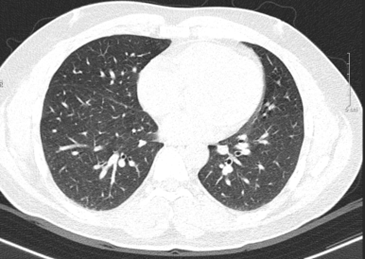

- Chụp cắt lớp vi tính lồng ngực sau điều trị 10 tháng: Nhu mô thùy trên sát rãnh liên thùy lớn có tổn thương dạng hang chứa khí kích thước 18x13mm, thành dày, có xơ hóa lân cận. Nhu mô phổi còn lại có vài nốt đặc, nốt lớn nhất đường kính 6mm. Phổi trái có vài nốt đặc bờ đều đường kính 5 mm.

Hình 3: Hình ảnh chụp cắt lớp vi tính lồng ngực sau điều trị 10 tháng: các nốt tổn thương gần hết và không có tràn dịch màng phổi